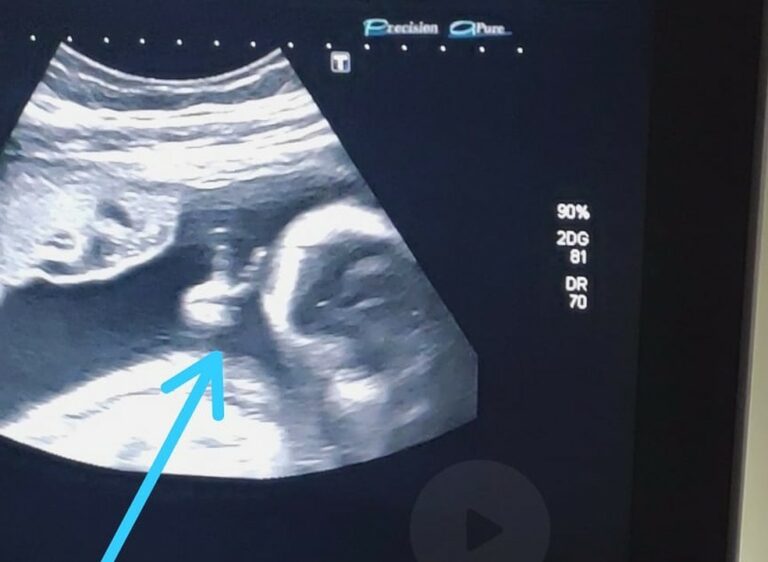

O rapaz conta que ver o ultrassom jĂĄ Ă© bem emocionante, porque consegue observar como o bebĂȘ estĂĄ e ouvir seu coraçãozinho. Mas, desta vez, ele se deparou com a surpresa de ver o filho Davi fazendo um sinal de ‘V’ com uma das mĂŁozinhas.

âAtĂ© a mĂ©dica falou: ‘olha, ele fez o sinalzinho de vitĂłria com a mĂŁo’. Eu fiquei sem acreditarâ, afirma. Ele encara a situação como um sinal divino de que vai conseguir superar o tratamento e vencer a doença.